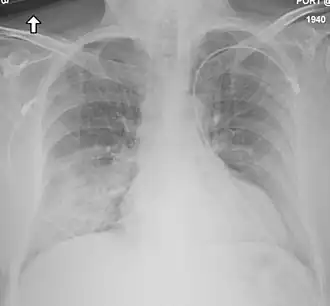

![]() Radiografía de tórax que muestra daño en los pulmones en un paciente con síndrome respiratorio de Oriente Medio. | ||